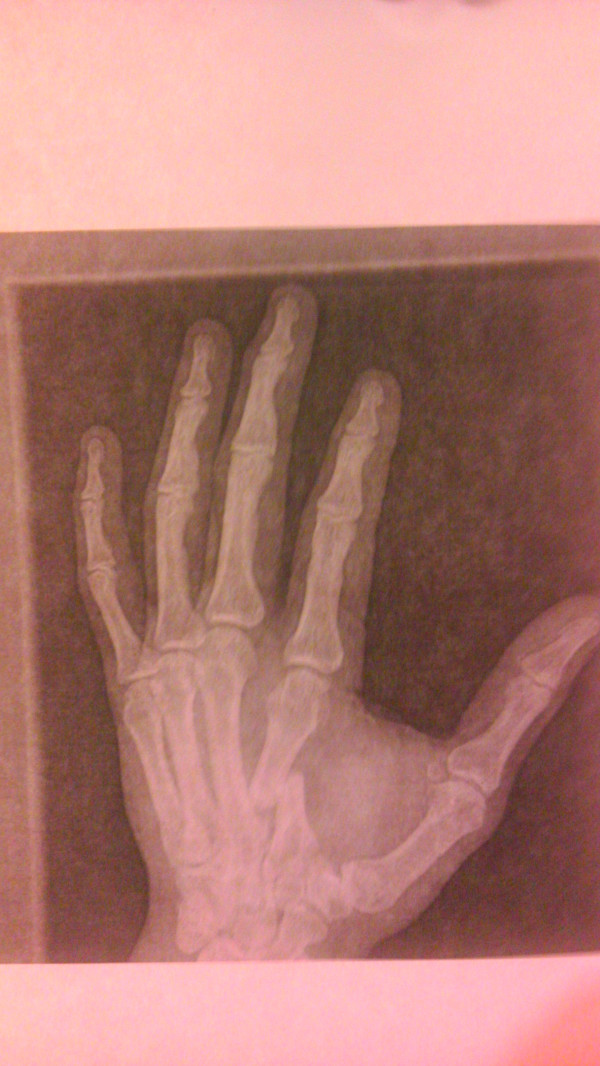

Quick Pic: X-ray of Josh Barnett's broken hand following Strikeforce Grand Prix loss to Daniel Cormier

Early in the first round of what would be a 25-minute fight against Daniel Cormier on Saturday night, Josh Barnett broke his hand with a punch. He appeared to be in excruciating pain once the fight was completed, but he battled through the injury and fought on for all 25 minutes.

Of course, he was beaten rather soundly in most of the rounds, and ended up losing the decision in the finals of the Strikeforce Heavyweight World Grand Prix, but he stuck in there and did as best he could with the injury throughout the fight.

On Sunday, he Tweeted out a picture of the X-ray, and it's easy to see why he was in such pain afterward. Still, it was a commendable effort considering all that Cormier was throwing and landing during the fight. Kudos to Barnett for trying to fight on despite this broken bone. Check out the x-ray below: